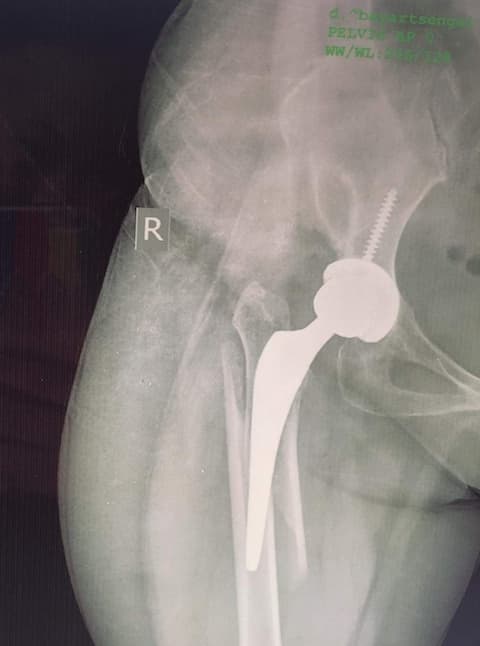

Total Hip Arthroplasty – үеийг бүтэн солих мэс засал

Хугарал засах мэс засал image9

УНТЭ-т хийгдсэн мэс заслын зураг